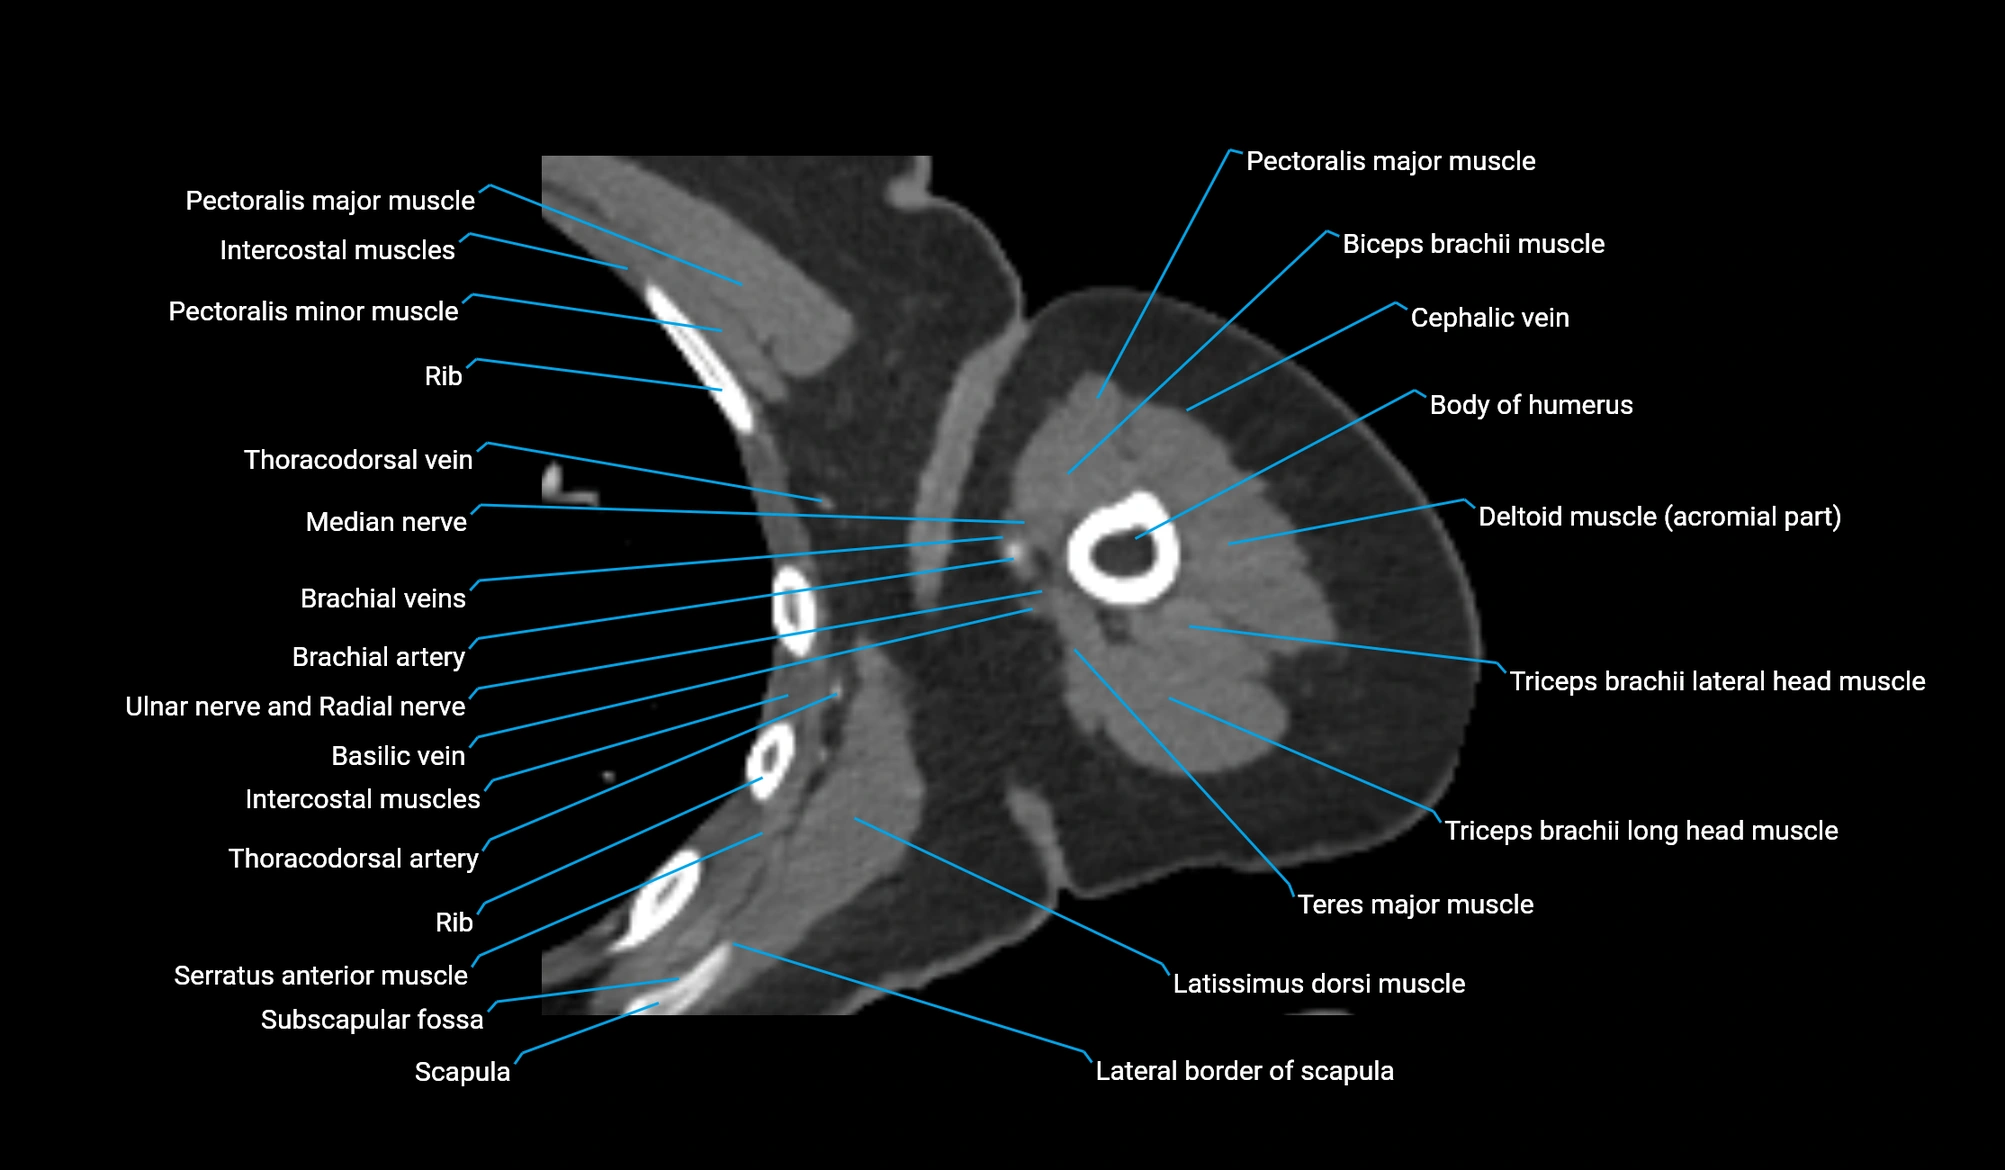

- Body of humerus

- Cephalic vein

- Lateral border of scapula

- Lateral head of triceps brachii muscle

- Long head of triceps brachii muscle

- Median nerve

- Pectoralis major muscle

- Pectoralis minor muscle

- Teres major muscle

- Thoracodorsal artery

- Triceps brachii muscle